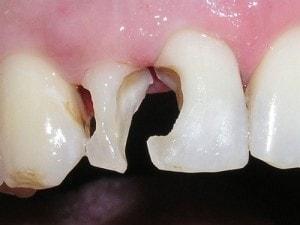

Restoration complicated by overlap

Contact is broken

Contact is broken with the blade end of a composite placing instrument. Matrix severed in the middle, and each segment lifted through the contact. Distal matrix segment can be seen being lifted through the contact (see arrow).